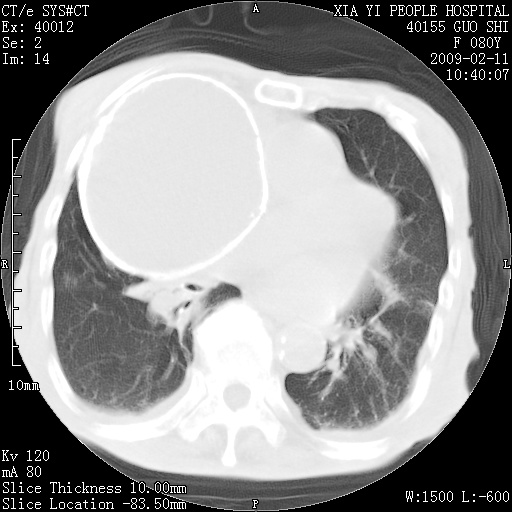

以下是引用随光逐影在2009-2-16 16:34:00的发言:[br]1)考虑右前纵隔皮样囊肿。2)双侧少量胸腔积液。

以下是引用zjzjr在2009-2-16 17:30:00的发言:[br]支持囊性畸胎瘤 双侧少量胸腔积液。